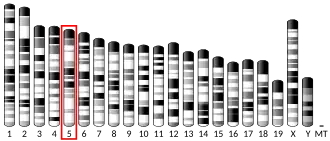

- Schanen NC, Scherer SW, Tsui LC, Francke U (1997). "Assignment of the 5-hydroxytryptamine (serotonin) receptor 5A gene (HTR5A) to human chromosome band 7q36.1". Cytogenetics and Cell Genetics. 72 (2–3): 187–188. doi:10.1159/000134184. hdl:10722/42533. PMID 8978771.